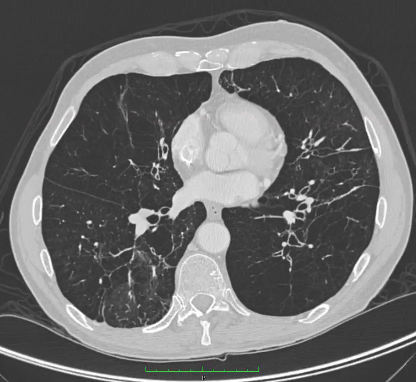

TC de enfisema avançado em paciente com deficiência de AAT

Da coleção pessoal de D. Kyle Hogarth, MD, FCCP; usado com permissão